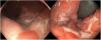

La forma de presentación en 13 casos fue una proctitis muy sintomática que motivó visitas a urgencias. Cuatro de los pacientes consultaron por lesiones genitales o masas inguinales. En uno de ellos la presentación clínica fue la aparición de 2 úlceras en el prepucio con linfedema doloroso asociado (fig. 1) y múltiples adenopatías en área del pubis. Otro paciente tuvo un absceso crónico en el pene con fistulización a la piel (fig. 2). En 2 pacientes el LGV se manifestó únicamente con bubones inguinales, en un caso con supuración secundaria a la piel y con un trayecto fistuloso hacia la zona escrotal (fig. 3). En las formas anorrectales los principales síntomas fueron el dolor espontáneo y el exudado purulento anal, aunque otros referían además tenesmo y sangrado. Los diagnósticos en las formas anorrectales de LGV fueron diversos: enfermedad inflamatoria intestinal en 4 pacientes, cáncer de ano en 2 pacientes y colitis infecciosa, fisuras, fístulas anales y hemorroides en el resto. En todos los casos se asociaba mal estado general y febrícula, y en 5 de ellos se comprobó pérdida de peso. No se encontró en ningún caso alteraciones en el hemograma ni en la bioquímica y en 14 pacientes en los que se realizó serología de C. trachomatis, esta fue positiva (IgG en todos los casos e IgM en uno de ellos).

En 9 pacientes con afectación anorrectal se practicó una rectosigmoidoscopia, que demostró úlceras extensas superficiales de límites geográficos en el canal anal y en la ampolla rectal (fig. 4). En las histologías de estos pacientes predominaron los patrones granulomatosos con infiltrados crónicos inespecíficos, asociados a criptitis aguda en 3 de los casos (fig. 5). No se evidenciaron microorganismos en las biopsias y las inmunohistoquímicas para citomegalovirus y Treponema pallidum fueron negativas. En el caso 1 se realizó una resonancia nuclear magnética que demostró edema de la mucosa rectal con obliteración de la luz con extensión al mesorrecto, asociado a múltiples adenopatías en las cadenas pararrectales e hipogástricas. En los casos de LGV clásico la ecografía fue de utilidad para demostrar y hacer un seguimiento de las adenopatías inflamatorias inguinales, así como de los abscesos y de las fístulas. En todos los casos se identificó el serovar L2 de C. trachomatis (con referencia en genbank CP002682.1) como agente etiológico.